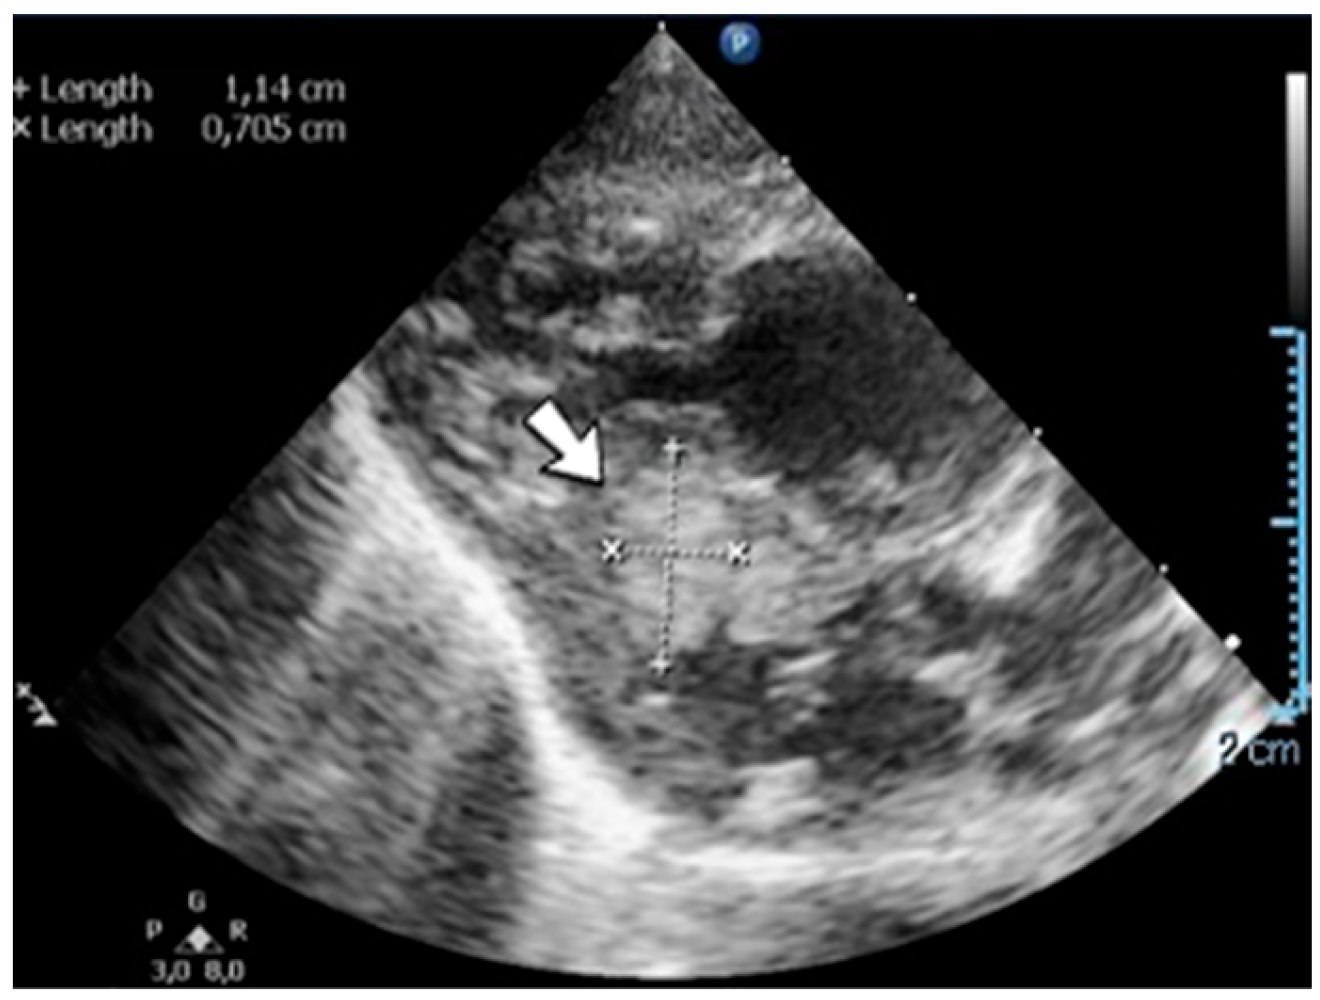

4.36. Case No. 36—Postnatal Intracardiac Thrombosis

A 7-week-old male infant (36 weeks, 2.50 kg), the first twin from a twin pregnancy, presented with a complex congenital cardiac malformation for an elective surgical procedure (Blalock–Taussig shunt). Heparin infusion for the shunt was started immediately after the intervention and anticoagulation was continued with enoxaparin due to good clinical condition. Then, 18 days after the procedure, a routine cardiovascular ultrasound revealed a thrombus in the left ventricle (Figure 16). The laboratory studies showed leukocytosis, highly elevated c-reactive protein, and modified coagulation tests (due to anticoagulant treatment). Continuous heparin infusion was reinitiated, but multiple intracardiac thrombi were detected during the following days. Treatment with alteplase was also started, but the patient’s condition continued deteriorating, leading to a negative outcome due to cardiac failure.

Figure 16.

Intracardiac thrombosis identified on cardiac ultrasound: left atrium and ventricle (A), left ventricle (B), apex (C).

Genetic testing confirmed inherited thrombophilia, with positive PAI-1 4G/5G promoter, MTHFR A1298C homozygous gene mutations, and Antithrombin and Protein C deficiencies. There was no known family history of thrombophilia. The mother had a previous therapeutic abortion due to a prenatal diagnosis of a complex congenital cardiac malformation.